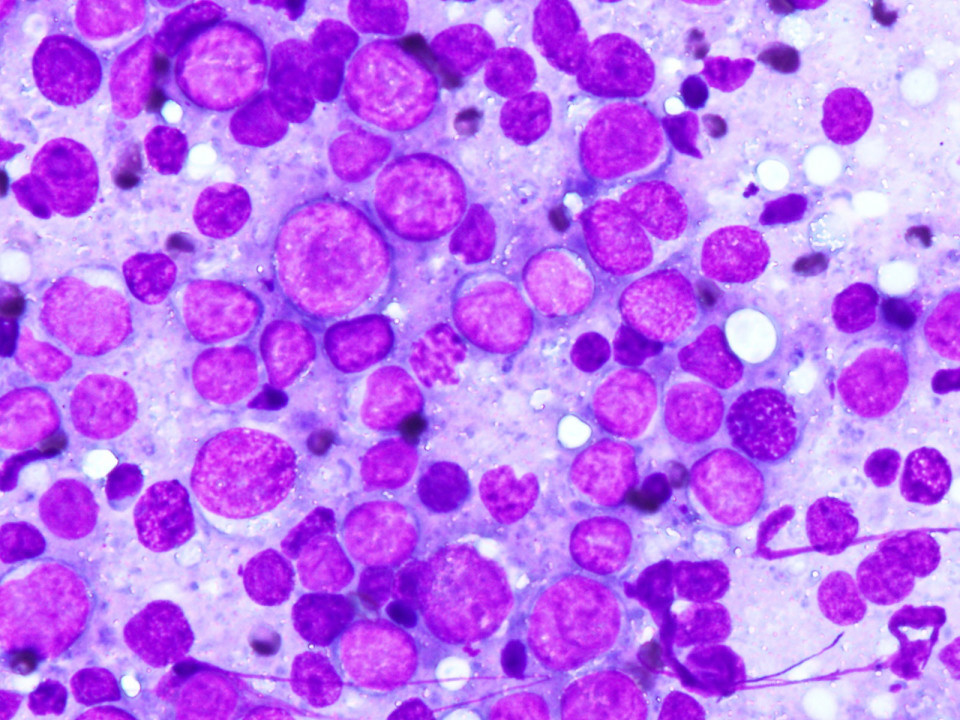

身体中にあるリンパ球ががん化する病気のリンパ腫。ヒトでは悪性リンパ腫と言われます。わんちゃん、ねこちゃんでは最も多い腫瘍の中の一つです。わんちゃんでは体の表層のリンパ腺が腫れる多中心型リンパ腫が最も多く、最近では胃腸にできる消化器型リンパ腫や皮膚・粘膜にできやすい皮膚型リンパ腫も増えているようです。ねこちゃんでは胃腸にできる消化器型リンパ腫にかかる場合が多く、他にも鼻にできる鼻腔型や胸の中にできる縦隔型などもあります。

リンパ腫のタイプによって治療法は異なりますが、抗がん剤を使った化学療法や局所的なものには放射線療法、抗がん剤と併用して免疫療法も行われます。

猫の消化器型高分化型リンパ腫。

高齢のねこちゃんで多い胃腸のリンパ腫。特にこの高分化型リンパ腫ではお薬の治療で長期にがんを抑えて普通の生活を送れることが多いです。

case.1

雑種猫、9歳齢、不妊雌。慢性の下痢、体重減少。組織生検にて高分化型リンパ腫の診断。

chlorambucil、predonisoneの内服治療。

症状消失、長期寛解生存。

case.2

case.1

結腸から直腸に発生した未分化型リンパ腫。

ミニチュアダックスフント、8歳齢、避妊雌。

肛門からの脱腸を繰り返し、結腸粘膜の組織生検で未分化型リンパ腫と診断。

L-CHOP療法を中心とした多剤併用化学療法を実施。寛解するも早期再燃し、ACNU、CCNU、DTICでサルベージ療法を実施。

結腸に発生した犬の高分化型リンパ腫。

雑種犬、9歳齢、避妊雌。組織生検による病理組織診断により高分化型リンパ腫と診断。

melphalan 0.05mg/kg sid-eod、predonisolone 0.5-1.5mg/kg sid 内服による治療で寛解。